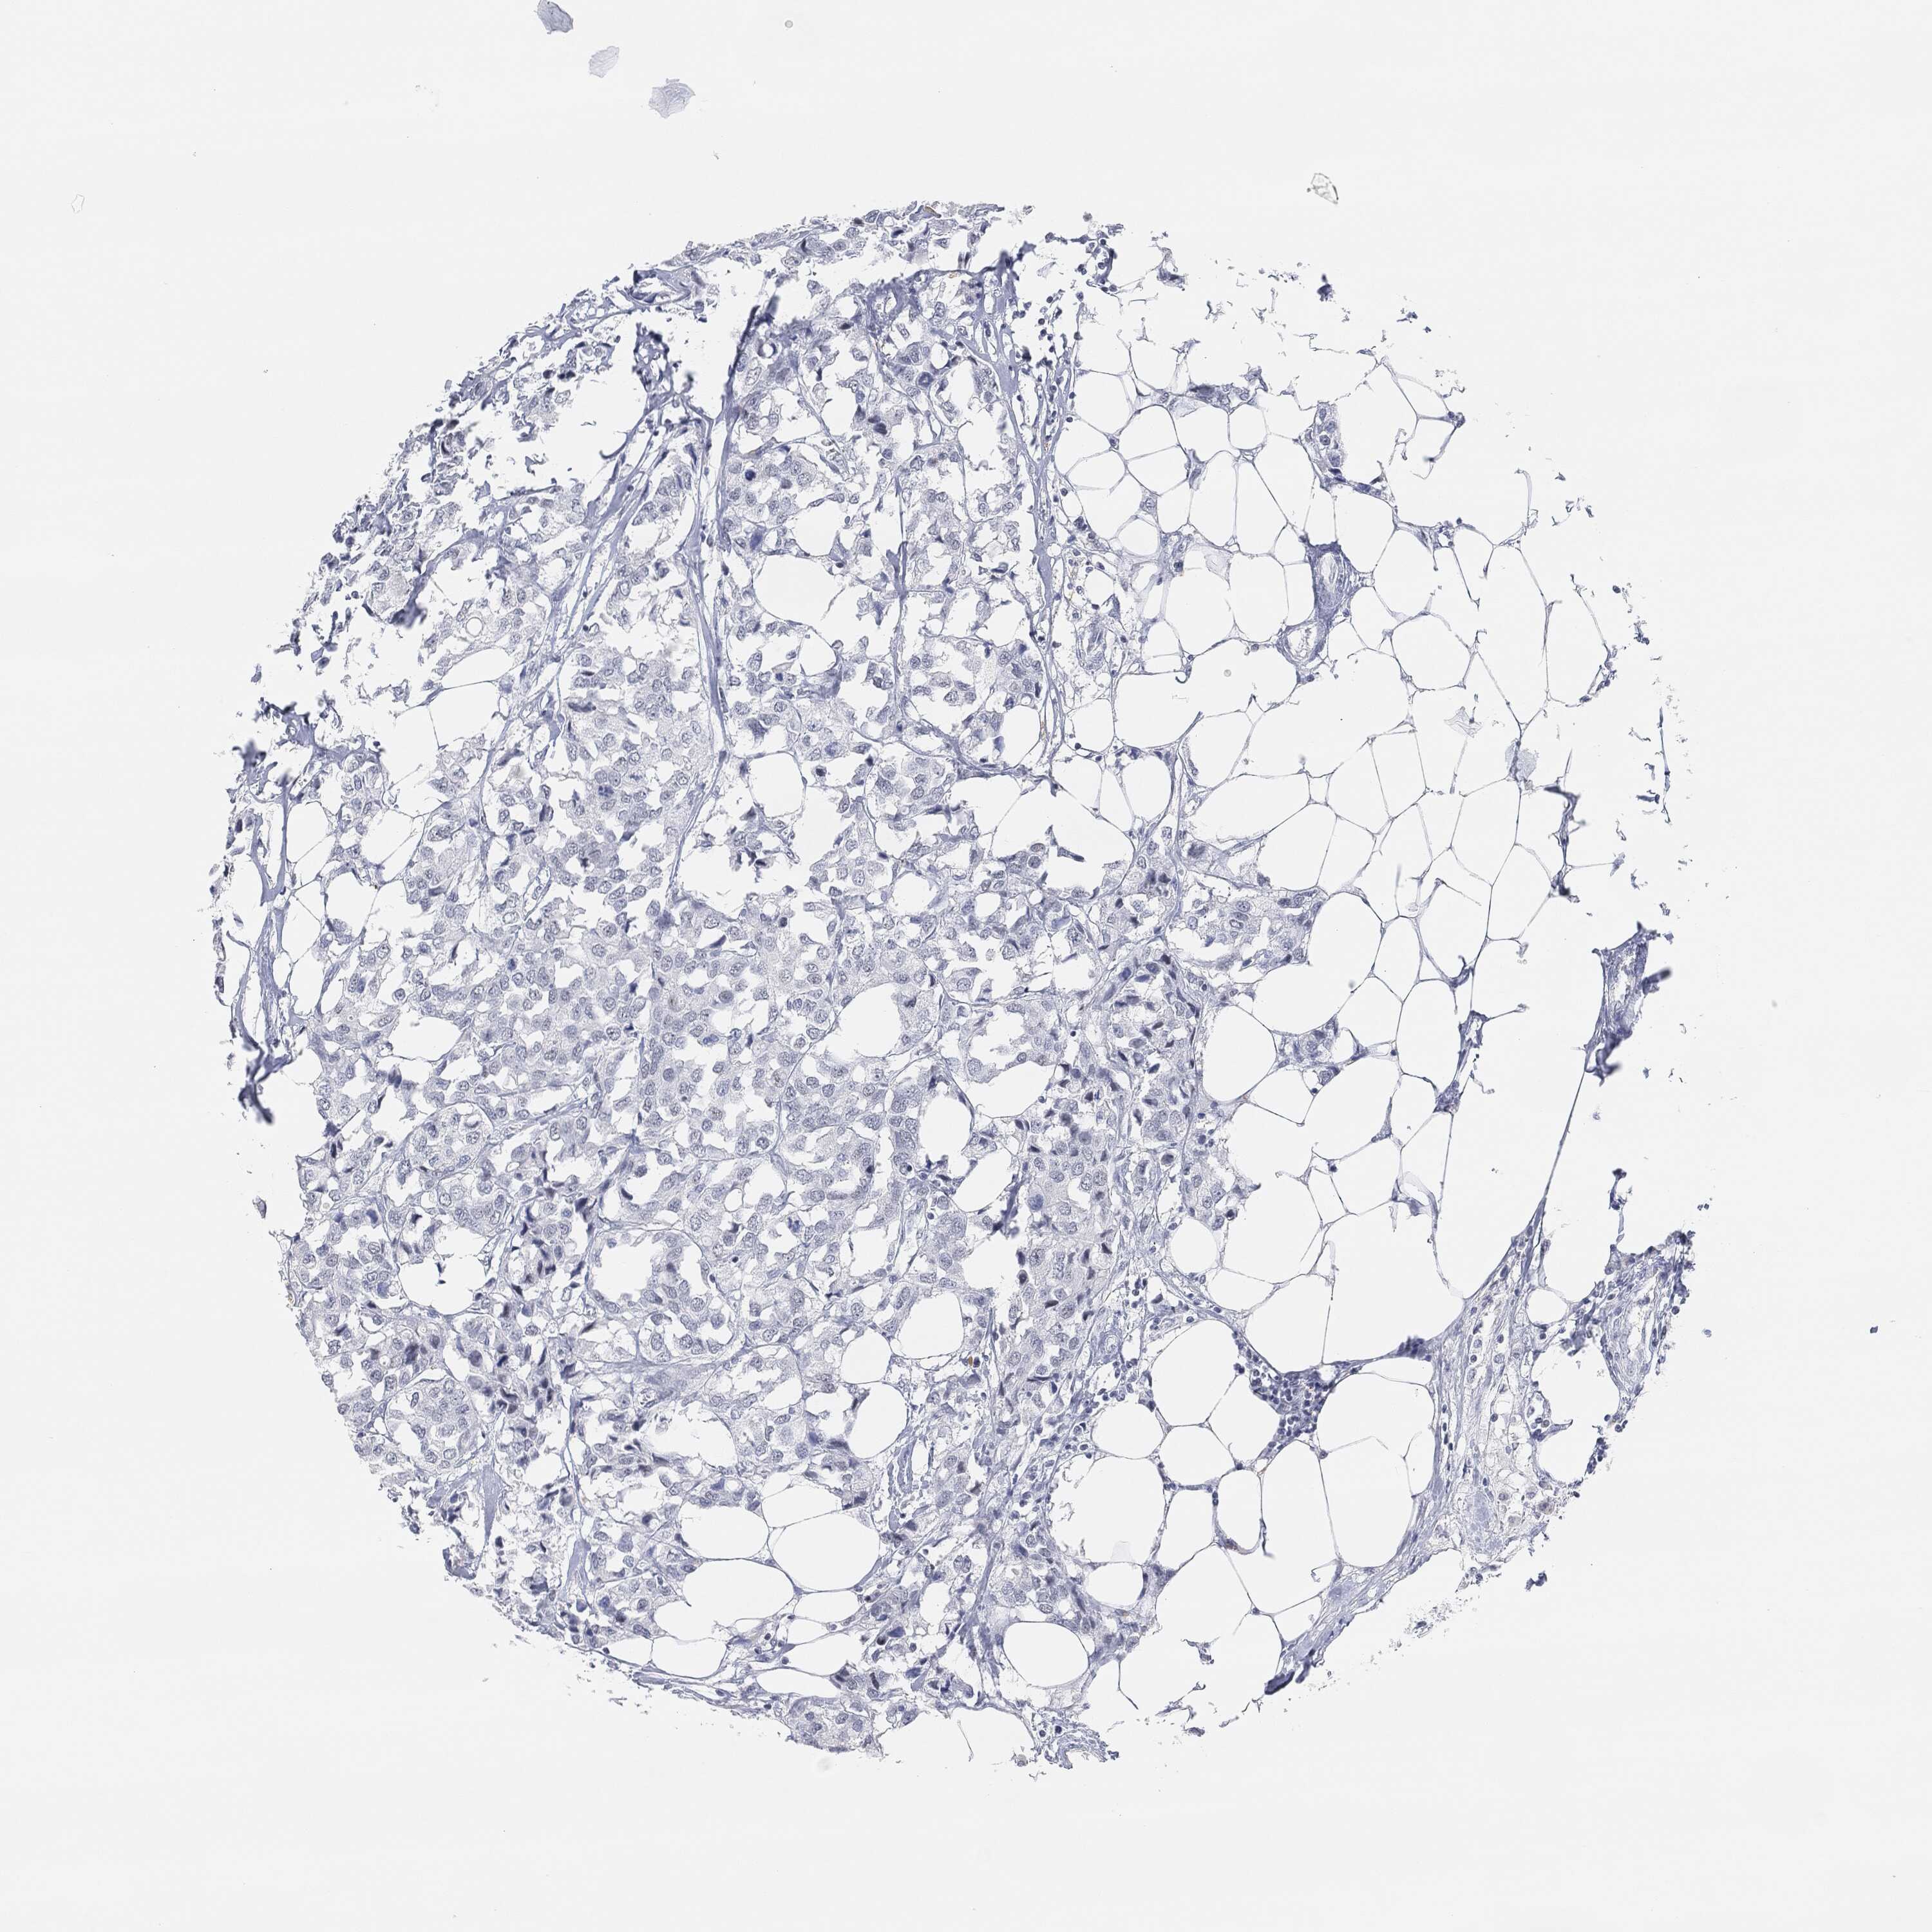

BRCA TCGA BRCA VALIDATION PROTEIN EXPRESSION

Breast cancer

Human cancer